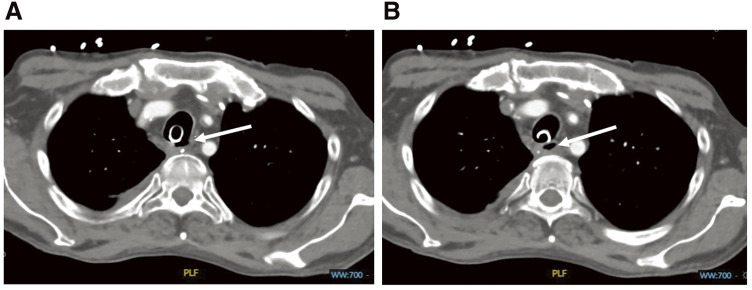

Case presentation: We report a case of a long tracheal membranous wall defect (> 7cm) after esophageal resection. We successfully performed a transtracheal direct repair of the defect through a partial sternotomy, and reconstructed the ventrolateral wall with a muscle flap using the right pectoralis major muscle.

Conclusion: Tracheal reconstruction through a T-shaped incision and anastomotic buttressing using a pectoralis major muscle flap could prove to be useful when reconstructing a posterior tracheal wall injury, especially after esophageal resection.